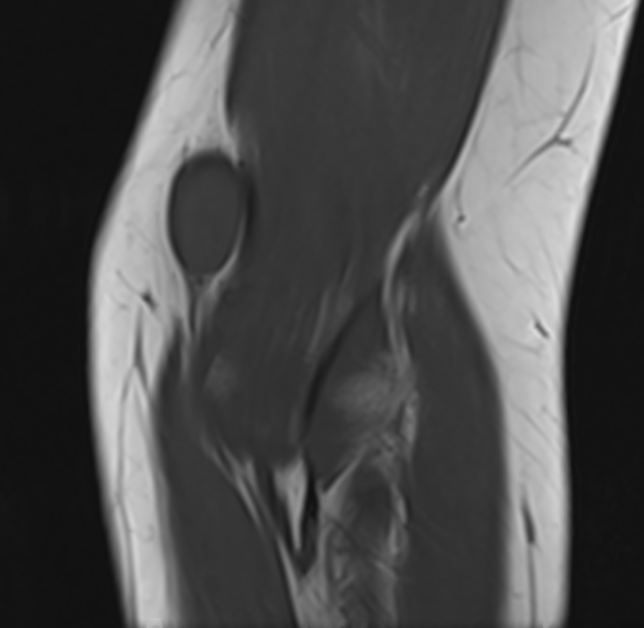

MRI

Target sign

- hypointense centrally

- hyperintense peripherally

Neurofibroma common peroneal nerve